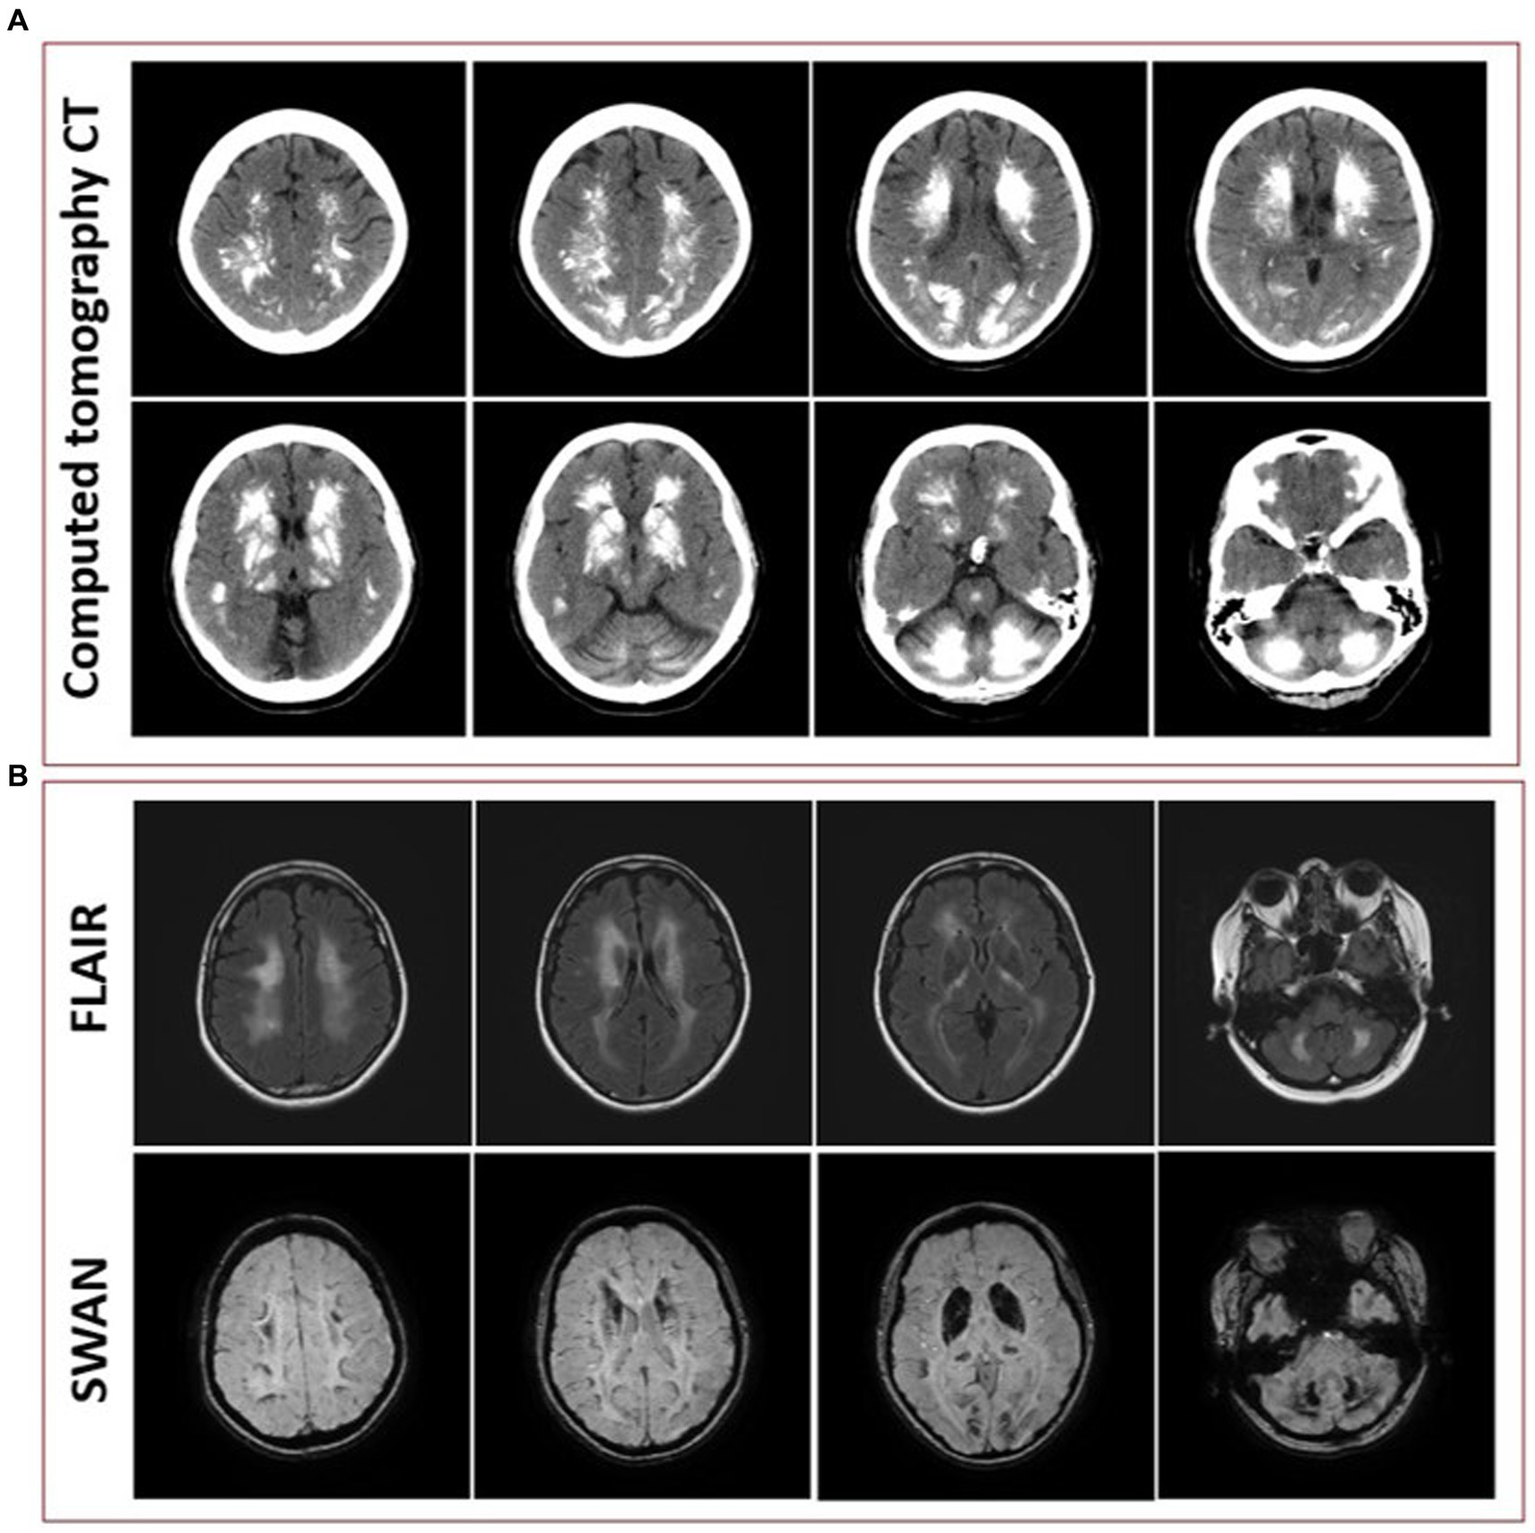

Initial blood work was ordered to exclude metabolic etiologies that might lead to brain calcifications, including parathyroid hormone, calcium, magnesium and phosphate, all of which were normal. A repeat CT scan of the head showed diffuse hyperdense foci favored to represent extensive calcifications throughout the bilateral corona radiata, basal ganglia, cerebellar hemispheres, and midbrain (Figure 3A), comparable to the patient’s initial neuroimaging 15 months prior. A repeat MRI brain without contrast showed extensive susceptibility effect and high T1 and T2 signal in the bilateral cerebral, brainstem, and cerebellar deep gray nuclei and white matter (Figure 3B).

Figure 3

(A) Representative axial cuts from the patient’s computed tomography (CT) scan 15 months after symptom onset, showing diffuse hyperdense foci favored to represent extensive calcifications throughout the bilateral corona radiata, basal ganglia, cerebellar hemispheres, and midbrain. (B) Representative axial cuts from the patient’s magnetic resonance imaging (MRI) 15 months after symptom onset, fluid-attenuated inversion recovery (FLAIR) sequence showing high T2 signal in the bilateral cerebral, brainstem, and cerebellar deep gray nuclei and white matter and susceptibility-weighted angiography (SWAN) sequence showing extensive susceptibility effect.